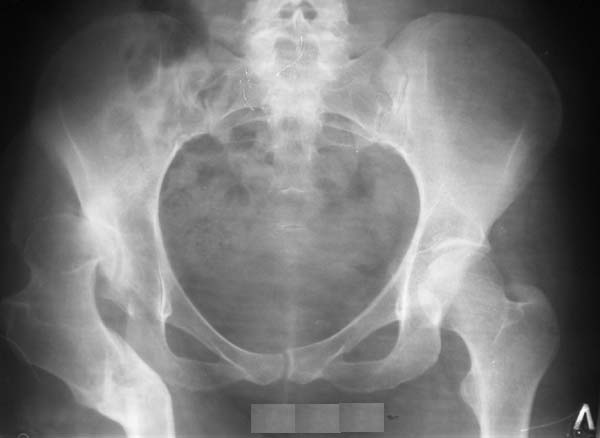

Уважаемые коллеги!Женщина, 35 летВ прошлом по поводу врожденного вывиха бедра перенесла операцию остеотомии по Шанцу

с удлинением правой ноги за счет бедра на уровне диафиза. В последнее время прогрессируют боли в правом тазобедренном суставе, порочное положение правой ноги, затруднена ходьба.Вопросы:1) Целесообразно ли эндопротезирование правого тазобедренного сустава?2) Целесообразный ли следующие действия: канал бедренной кости предполагаем вскрыть для введения ножки протеза на высоте угловой деформации, предполагаем низведение большого вертела с мышцами; протез будет подобран индивидуально, предполагается умеренная версия?В приложении рентгенограммы и трехмерная КТ.В цветном и более качественном варианте КТ размещена здесь

Похожий случай представляем на ретгенограммах. Операция выполнена в 1996 г.